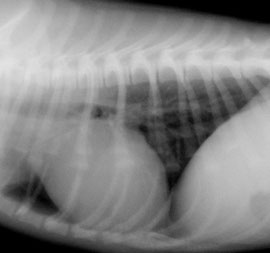

下記は以前のレントゲンシステムで撮影した画像と新しいレントゲンシステムで撮影した画像の比較です。

クリックして拡大していただくと、骨の鮮明さ、心臓の血管の見え方が新しいレントゲンシステムのほうが良くご理解いただけるかと思います。

以前のレントゲンシステムで撮影した画像